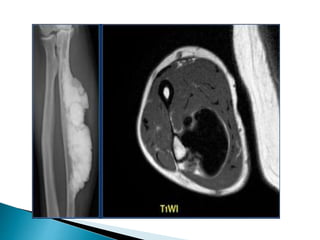

 The radiograph shows typical bone infarcts

in diaphysis and metaphysis of femur and

tibia.

 On MR imaging bone infarcts are

characterized by irregulair serpentiginous

margins with low signal intensity on both T1

and T2 WI and with intermediate to high fat

signal in the center part.

 Enhancement after i.v. Gadolinium is usually

minimal or absent.

At the periphery of the infarct a zone of

relative high signal intensity on T2WI may be

found..

 The radiographshows typical bone infarcts in diaphysis and metaphysis of femur and tibia.  On MR imaging bone infarcts are characterized by irregulair serpentiginous margins with low signal intensity on both T1 and T2 WI and with intermediate to high fat signal in the center part.  Enhancement after i.v. Gadolinium is usually minimal or absent. At the periphery of the infarct a zone of relative high signal intensity on T2WI may be found..

 Differentiating abone infarct from an enchondroma or low-grade chondrosarcoma on plain films can be difficult or even impossible. Cartilaginous tumors in particular chondrosarcoma may show endosteal scalloping, while a bone infarct does not. Chrondroid tumors are more frequently encountered than bone infarcts.